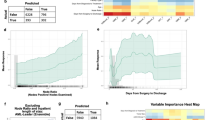

In the five ML models established using preoperative clinical data, the top commonly selected factors such as non-PDAC etiology, small pancreatic duct size, low glucose level, high hemoglobin, and high VATI for POPF occurrence (Fig. 2). Preoperative CT-based four DL models were developed, and gradient-guided class attention maps showed the areas that the models focused on (Fig. 3). The finally selected model was the soft voting-based ensemble model composed of two ML models (ANN and logistic regression) and one DL model (Inception Net). AUCs of the ensemble model in the training, validation, and test datasets were 0.969, 0.779, and 0.750, respectively. Sensitivity, and specificity were described in Supplementary Table 7. The Roberts model was not included in the ensemble model. The predictive performance of the ensemble model was enhanced as compared to individual ML and DL models.

SHAP summary plots of relative feature importance of the selected machine learning models. (A) preoperative postoperative pancreatic fistula model, (B) preoperative clinically relevant postoperative pancreatic fistula model. Plots order the features based on their importance. Each plot is made up of individual points from the training dataset with a high value being redder and a low value being bluer. POPF postoperative pancreatic fistula, PDAC pancreatic ductal adenocarcinoma, Hb hemoglobin, VFAT visceral adipose tissue index, HTN hypertension, DM diabetes mellitus, SMA.hu.b intramuscular adipose tissue index, BMI body mass index, WBC white blood cell, Cr creatinine, SHAP sharply additive explanations, CR-POPF clinically relevant postoperative pancreatic fistula, SFAT_I subcutaneous adipose tissue index.

In the preoperative CR-POPF model, ML models frequently selected non-PDAC etiology, high VATI, absence of diabetes, and smaller pancreatic duct size as important factors predicting CR-POPF. The selected hard voting-based ensemble model comprised three ML models (ANN, TabNet, and random forest) and two DL models (ResNet and ResNeXt); the Roberts model was not included. AUCs of Ensemble model in the training, validation, and test datasets were 0.936, 0.915, and 0.682, respectively, and the ensemble model showed better predictive performance than individual ML and DL models (Table 2).

The predictive performance of the Roberts model and the preoperative ensemble model were compared to preoperatively predict POPF, and the preoperative ensemble model showed better performance (AUC, 0.750 vs. 0.637; p < 0.001); however, comparable predictive performance was observed between the preoperative ensemble and Roberts models for CR-POPF prediction (AUC, 0.682 vs. 0.635; p = 0.42). (Table 2, Fig. 4).

Predictive performance of artificial intelligence models and conventional prediction models for postoperative pancreatic fistula in the test dataset. Receiver operating characteristic curves of the ensemble models (red), machine learning models (yellow), deep learning models (orange), and prior models (Roberts model [green]) are plotted. The ensemble models showed the best predictive performance for preoperatively predicting all postoperative pancreatic fistula (A) and clinically relevant postoperative pancreatic fistula (B). POPF postoperative pancreatic fistula, CR-POPF clinically relevant postoperative pancreatic fistula, DL deep learning, ML machine learning.

Changing AUC pattern according to the CR-POPF incidence

The low ratio of CR-POPF could affect model development because of the potential bias toward major cases and the negative impact of the model’s ability to learn. In this study, the CR-POPF incidence was relatively lower than that in other institutions, and we investigated changing pattern of model performance when the ratio of control and event were adjusted from 6.5% to 50%. The preoperative ensemble model for CR-POPF showed optimal performance AUCs regardless of the incidence ratio of CR-POPF, whereas the AUC of the Robert models decreased to approximately 30% of CR-POPF (Fig. 5).

Changing pattern of area under the curve value according to the clinically relevant pancreatic fistula incidence. The value of area under the curve of the ensemble models (yellow), machine learning models (gray), deep learning model (orange), and conventional models (Roberts model [blue]) for clinically relevant pancreatic fistula are plotted. Preoperative ensemble model for clinically relevant pancreatic fistula showed AUC ≥ 0.7 after 18% of the clinically relevant pancreatic fistula rate; AUCs of the ensemble model showed better performance than other models.